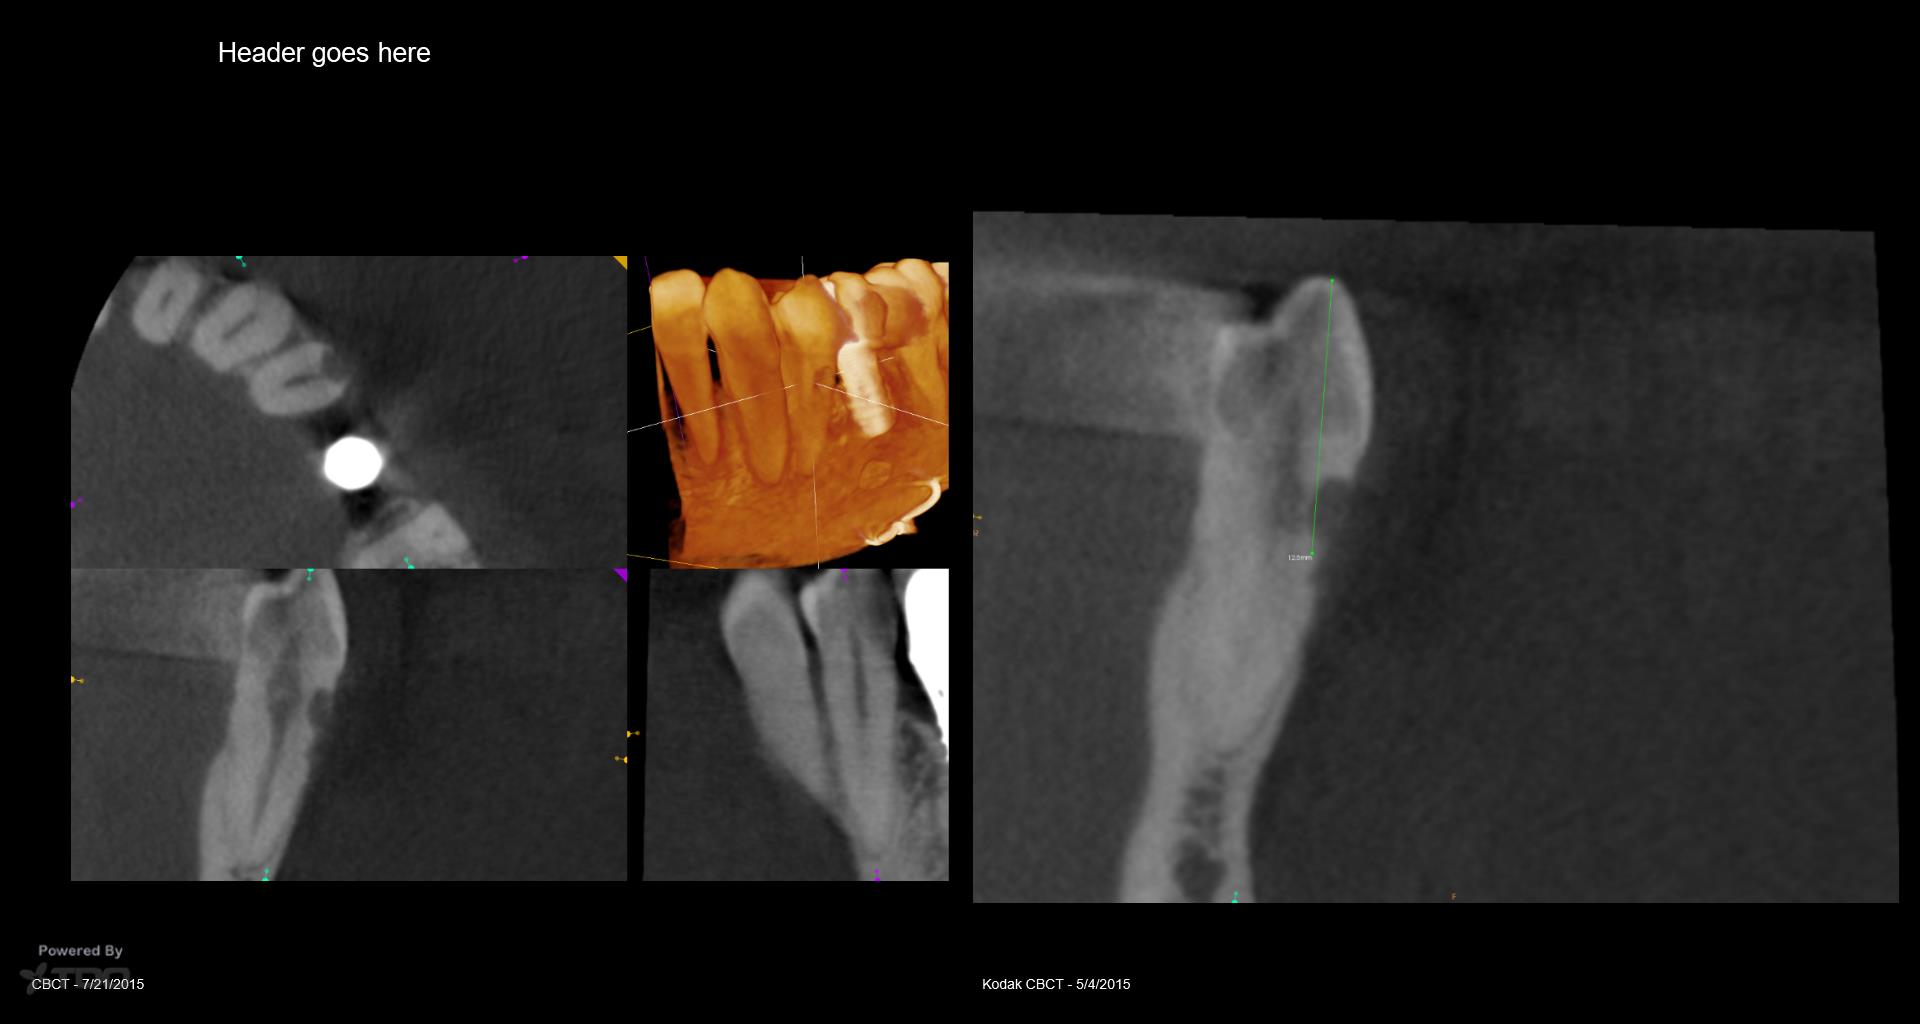

I struggled with the composite. I think I could do it better today but at least the repair seems to be holding. The defect went from line angle to line angle–the whole buccal face of the tooth. . gbc